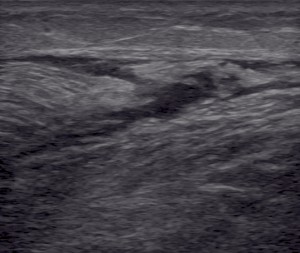

ecografía musculoesqueletica